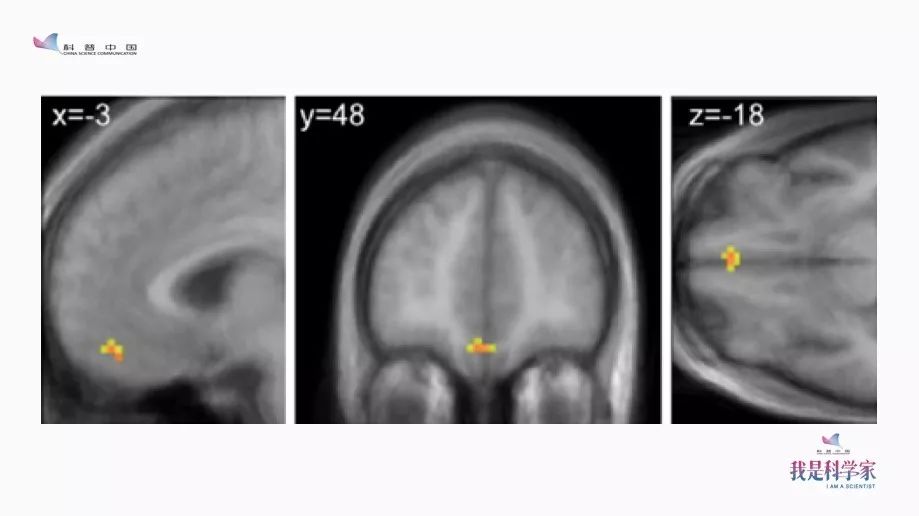

我就去请教那些搞神经科学的哥们儿:我们看到账单的时候,大脑是什么反应?他就给我看了这张图。

图中有个区域叫做Insula(脑岛)。收到账单时,我们的脑岛就会被激活。不只是收到账单,其他时候,比如在赌博中输钱时,逛街看到一个高到离谱的价格标签,我们的脑岛也会被激活——还有什么时候,我们的脑岛会被激活?当我们被人打了一耳光的时候,脑岛也会被激活,因为这个时候很痛,而脑岛也是疼痛中枢的一部分。因此,卡耐基梅隆大学非常有名的经济心理学家George Loewenstein就说过:你收到一份账单,这和打你一巴掌是一样的。所以,支付宝每年年底都会啪啪打我们的脸,太不厚道了。